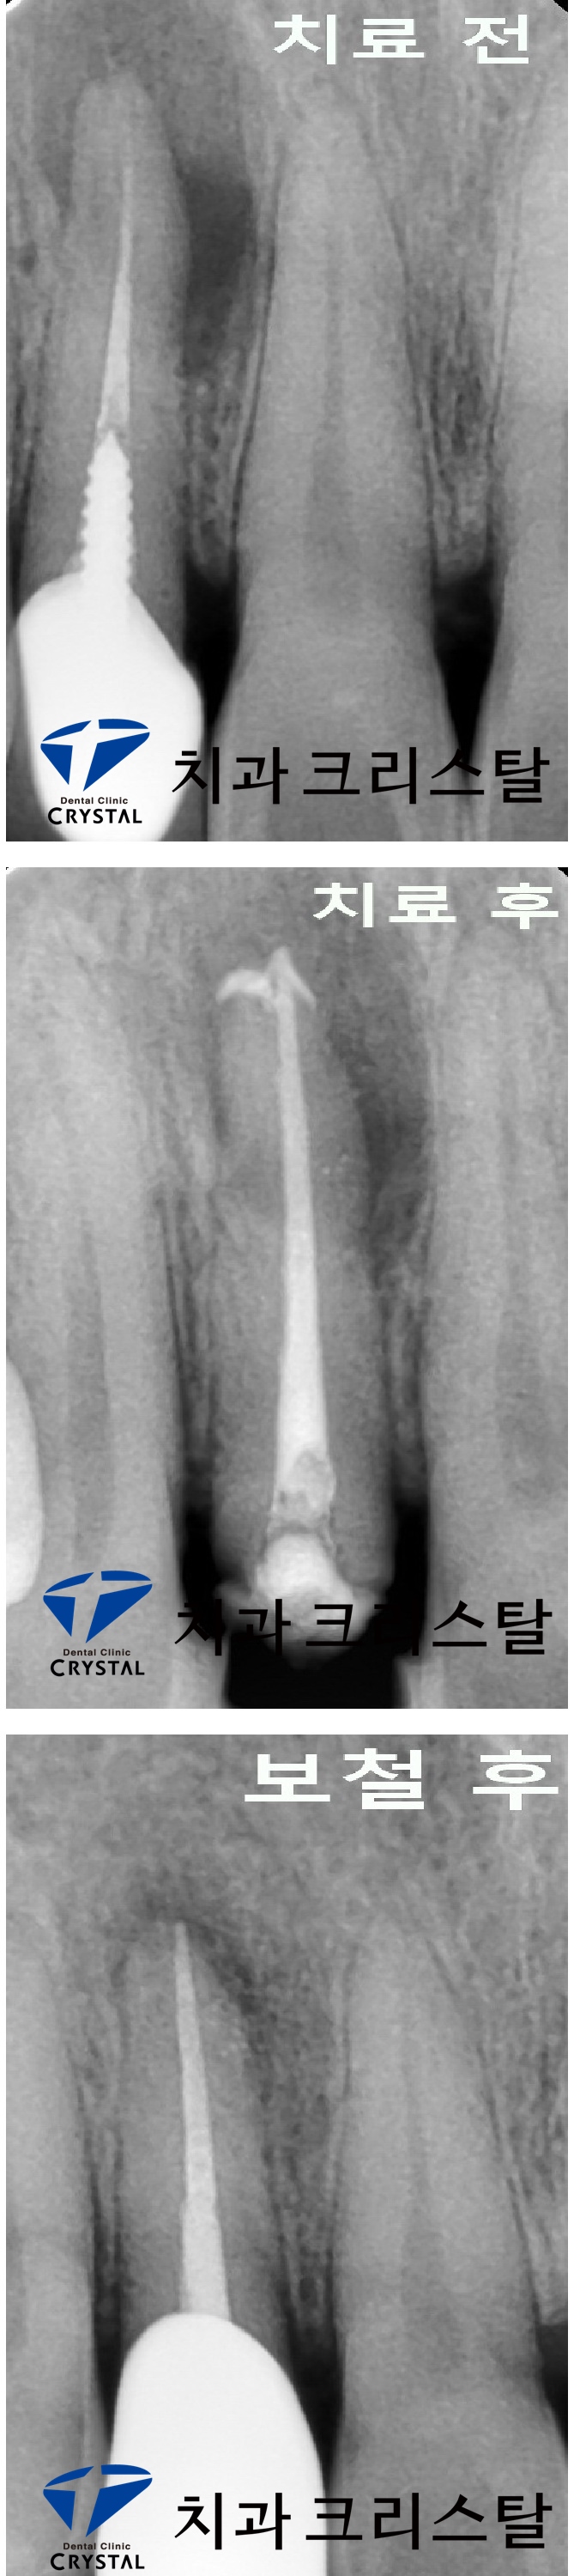

오래 전 근관치료 후 크라운을 한 치아의 뿌리 끝에 큰 염증이 생기고, 고름이 나오는 상태의 치아였습니다.

금속 기둥을 제거 & 재 근관치료를 하고, 다시 기둥으로 보강 후 짧아진 치아 길이를 길게 하기 위한 잇몸 수술을

한 후에 크라운을 다시 하였습니다.

재 근관치료 후 뿌리 끝에 있던 염증으로 인한 뼈 소실 부위가 치유 된 것을 확인할 수 있습니다.